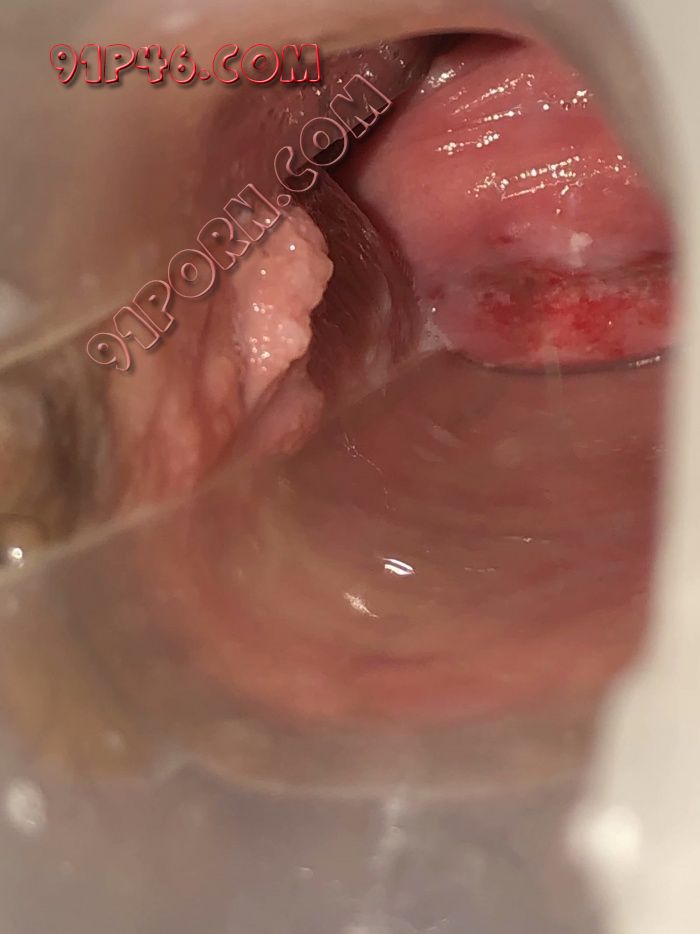

论坛里,有没有医生朋友帮看一下小骚货的逼是不是坏掉了

1、生过孩子或者打过胎

2、轻度宫颈糜烂3、没有发炎

做一下HPV筛查

那么红肯定有炎症了,最好是去正规医院做个妇科检查的好。另外阴唇看着不黑嘛

不听楼上瞎说,宫颈糜烂就是个骗局,都是莆田系医院编出来骗钱的。应该叫宫颈柱状上皮异位,这是指因雌激素的作用,宫颈管柱状上皮外移至宫颈外口的一种现象,这是一种正常的生理现象。

不用去医院看,宫颈糜烂不是病,不用看。而且你这个是轻度的。

它是因为激素引起的,注意卫生定时体检即可。

这就是轻微的宫颈糜烂,不算很严重,建议去医院开一些洗剂冲洗,温水清洗